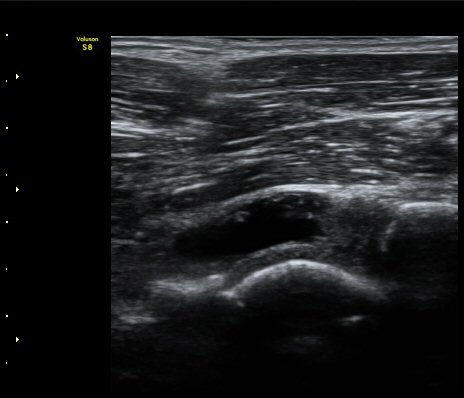

[ÆÈ²ÞÄ¡] ÆÈ²ÞÄ¡ °üÀý³» À¯¸®Ã¼¿¡ ÀÇÇÑ ÆÈ²ÞÄ¡ ÅðÇ༺ °üÀý¿°

¼ºº° / ³ªÀÌ

³²ÀÚ/ 44¼¼

ÁÖÁõ»ó

ÆÈ±ÀÄ¡ ÅëÁõ

ÃÊÀ½ÆÄ °Ë»ç